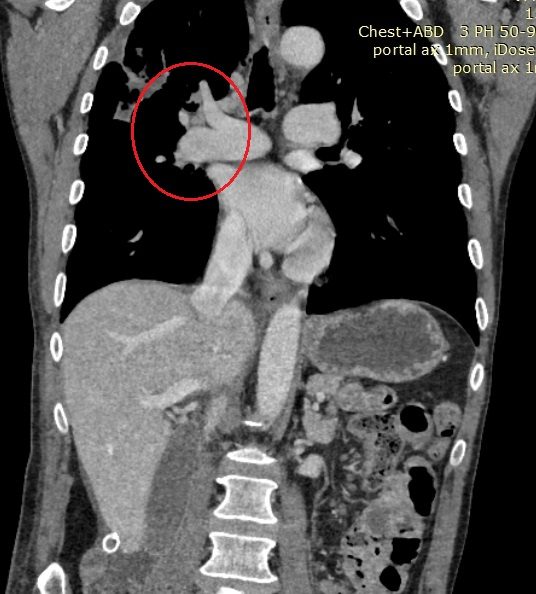

Приангио-КТ груди, живота, малого таза от 3.09.2020 — КТ-картина эмболии правой легочной артерии и ее ветвей, инфильтрат в S2 правого легкого с наличием полостей деструкции в структуре, участки консолидации легочной ткани в S1, S2, S3 правого легкого, один из которых с полостью деструкции с учетом наличия тромботических масс в артериях А1, А2, А3 справа более вероятно соответствует инфаркт-пневмонии с полостями деструкции (рис. 2, 3). КТ-картина образований правой почки — с наличием неоднородных тромботических масс в правой почечной вене, НПВ (опухолевого генеза), омываемых со всех сторон.

Рис. 2. КТ-ангиограмма груди пациента Г.Овалом указаны окклюзирующие эмболические массы в просвете правой легочной артерии.